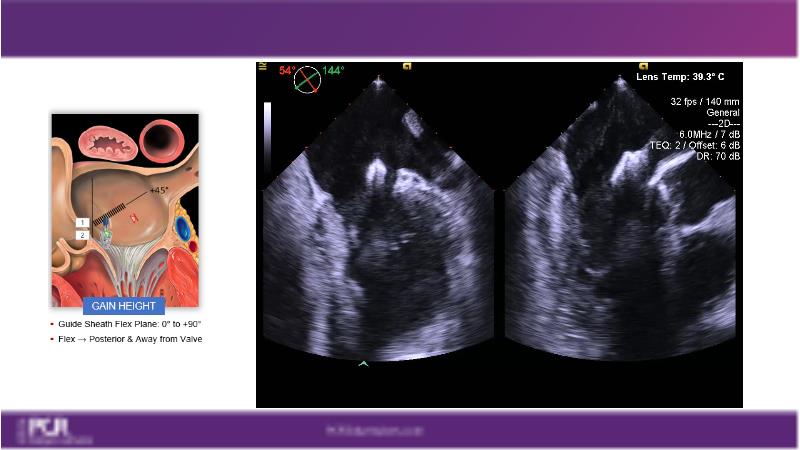

Watch this session to get an overview of a new TEER device, follow the step-by-step procedure related to initial experiences with this device for a Japanese patient with degenerative mitral regurgitation, learn about the latest data from RCT and registries, and follow discussions of challenging TEER cases!

- To learn procedural step-by-step of novel device